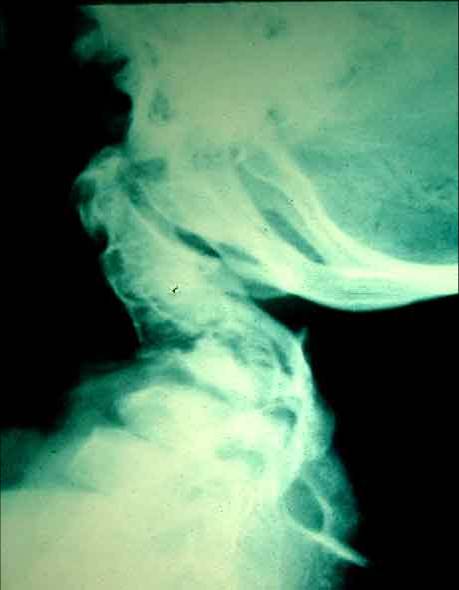

• severe cervical kyphosis

• AP and lateral of cervical spine and thoracolumbar spine

• cervical kyphosis frequently resolves spontaneously

• posterior cervical fusion

• indications

• cervical kyphosis that does not resolve spontaneously